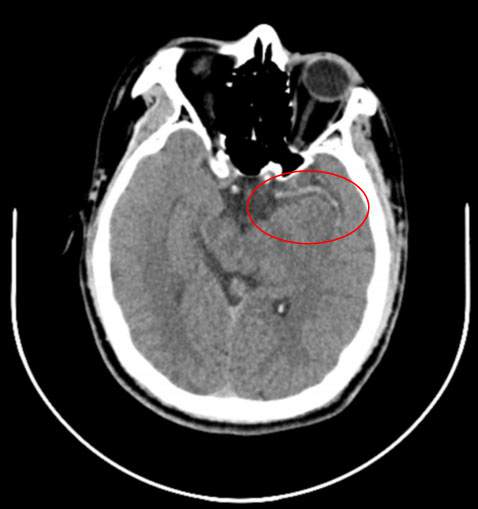

急诊复查CT:

未见确切急性脑梗塞,但左侧大脑中动脉主干全程密度显著升高,提示闭塞。